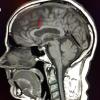

Corpus Callosum Notch